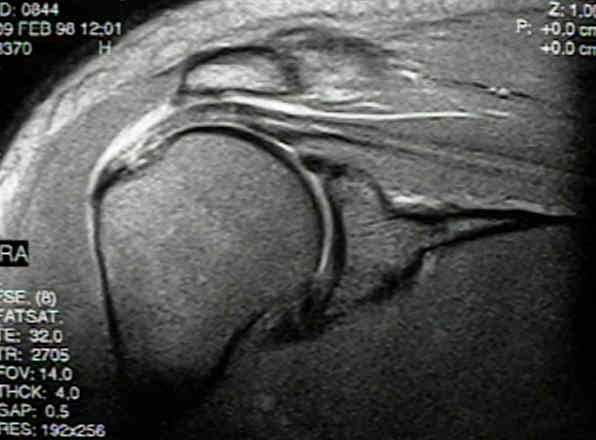

Seeing Patients in Our Groundbreaking Shoulder Rotator Cuff Stem Cell Trial

I examined a patient yesterday in clinic for our shoulder rotator cuff stem cell trial. She was randomized to wait three months and has been engaged in home exercises for her full thickness rotator cuff tear. Since she still has issues with returning to full activity, she’s been cleared to get the actual stem cell…read more